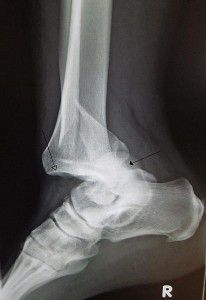

Se hace mediante una exploración radiológica en los dos planos, en la que se ve la pérdida de contacto permanente de las superficies articulares, total o parcial. Si bien, en muchísimas ocasiones se evidencia por signos externos como deformidad, posturas especiales, etc. como el hombro en charretera en la luxación de hombro.